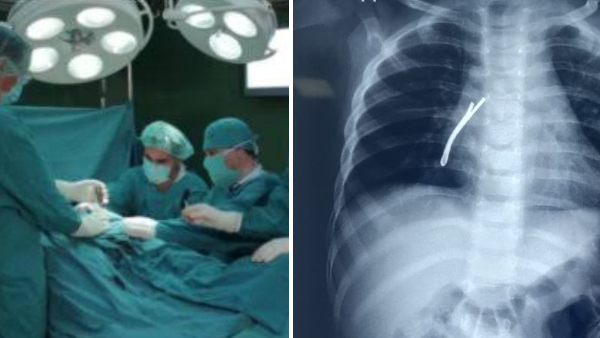

एम्स के डॉ विकास गुप्ता ने जानकारी देते हुए बताया कि हमने बच्चे की जांच के लिए ईएनटी सर्जनों की टीम बनाई। इसके बाद गहन जांच की गई। उसकी छाती की इमरजेंसी रेडियोग्राफी कराई गई। वही हाई रेगुलेशंस सीटी (कंप्यूटेड टोमोग्राफी) की गई। जिसकी रिपोर्ट सामने आने के बाद बच्चे के दाहिने फेफड़े यानी राइट ब्रोंकस की श्वास नली के निचले हिस्से में एक लंबा हेयर पिन फंसा दिखाई दिया।

इसके बाद टीम ने बच्ची को ऑपरेशन थिएटर के लिए रेडी किया गया। बच्ची को पहले सामान्य एनेस्थिसिया दी गई। इसकी मदद से बच्ची की आपातकालीन रिजिड ब्रोंकोस्कोपी की गई। बच्चे की दाहिनी तरफ श्वसन नली यानी ब्रोंकस से ऑप्टिकल चिमटे का उपयोग करते हुए हैरपीन को निकाला गया। यह हैरपीन करीब 4 सेंटीमीटर लंबी थी डॉक्टरों के मुताबिक श्वास नली में इस तरह की कोई भी भारी वस्तु फंस जाए तो वह जानलेवा हो सकती है।

डॉ विकास गुप्ता के नेतृत्व में की गई सर्जरी में ईएनटी की ऑपरेशन टीम के डॉक्टर उत्कल पी मिश्रा, डॉक्टर गणकल्याण बेहरा, डॉक्टर राहुल वर्मा डॉक्टर अंगम और डॉक्टर रशमा और एनेस्थिसिया डॉक्टर जेपी शर्मा डॉक्टर पूजा सिंह व डॉ रिया इसके अलावा डॉ सोविक और थॉमस शामिल रहे। बता दे इस सफल ऑपरेशन के लिए डॉक्टरों की टीम की भोपाल में जमकर तारीफ की जा रही है। चिकित्सा शिक्षा मंत्री विश्वास सारंग ने डॉक्टरों के सफल ऑपरेशन के लिए बधाई दी है।